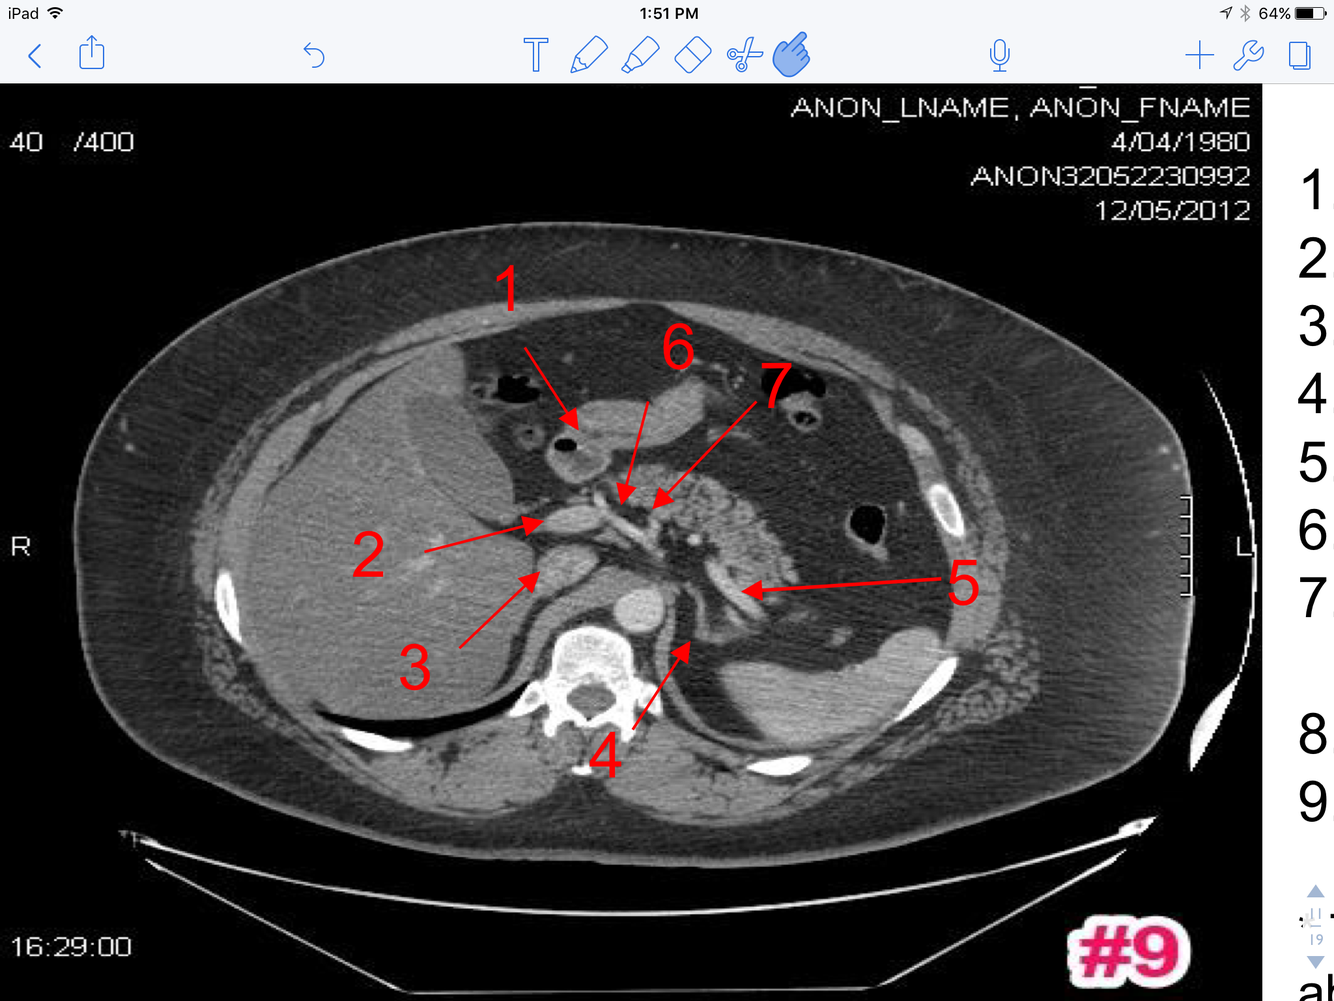

12

Q

A

1. Superior mesenteric artery

2. Superior mesenteric vein

3. Lt. renal vein

4. Rt. renal artery

5. Upper pole right kidney

13

1. Transversus abdominus muscle

2. Lt. Internal abdominal oblique M

3. Lt. External abdominal oblique M

4. Rectus Abdominus

5. Rt. Renal A

6. Lt. Renal A

7. Lt. Renal V

8. Superior mesenteric A

9. Superior mesenteric V